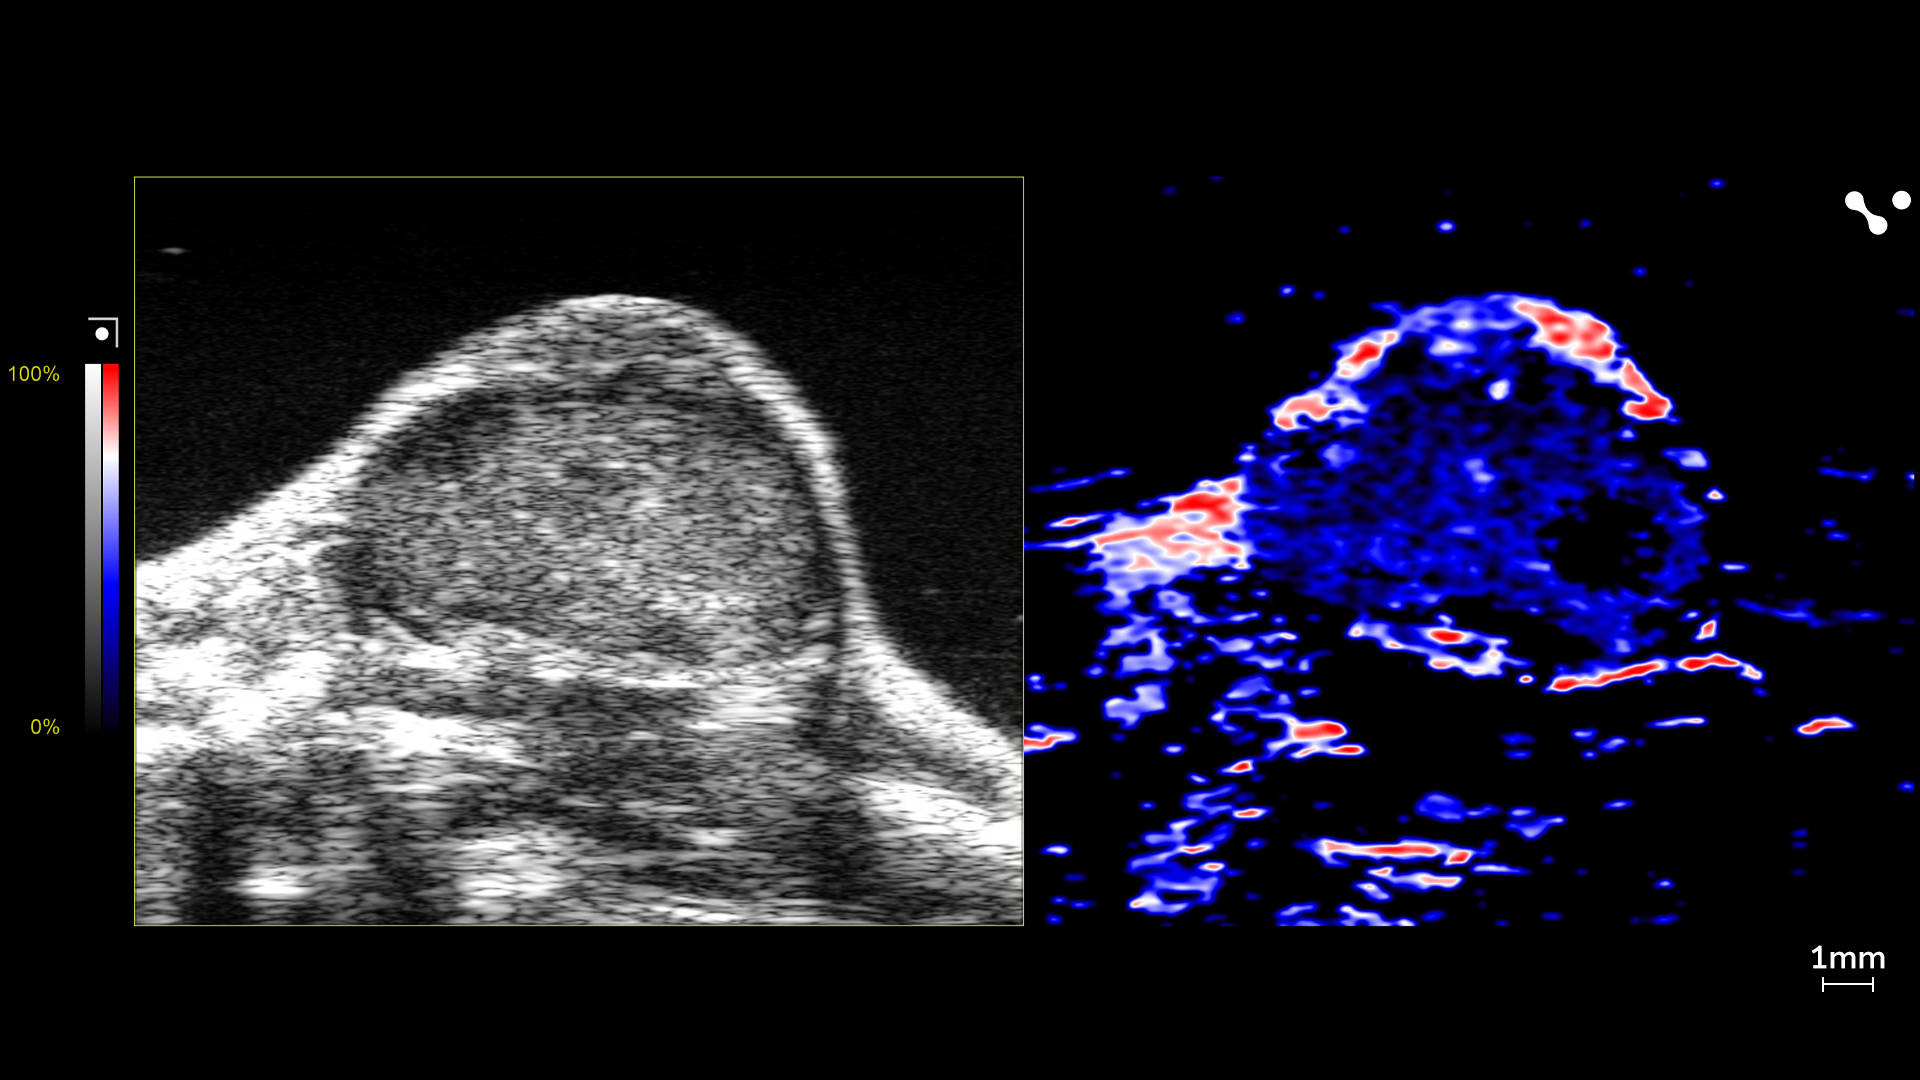

Four ultrasound images showcasing the difference between the control mouse and the NAFLD/MASLD mouse.

Shear Wave Elastography Mode

Easily switch between visualizing stiffness and velocity; see the difference between a healthy liver and a fatty liver.